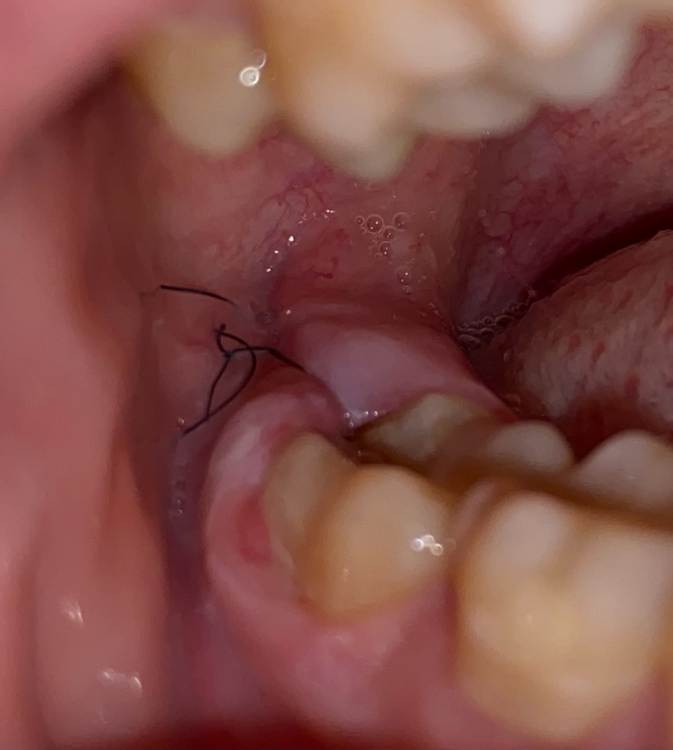

на фото рана еще с одним швом, но его сегодня сняли

промывают начиная от десны, которая граничит с 7 зубом

не повредит это ему? Потому что десну постоянно отодвигать приходится и промыватьA90B660C-70D6-4B8B-989F-7E5D3A48886B.thumb.jpeg.8e542ee23994d1972c1e1b8133c0e429.jpeg